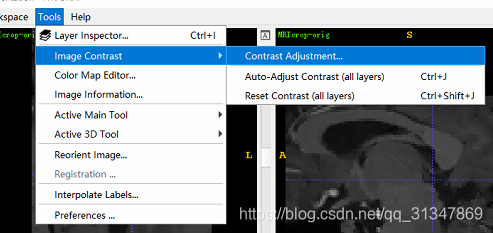

调整图像对比度:Tools -> Image Contrast -> Contrast Adjustment

绘图区域显示了图像强度和现实强度的映射,如红线所示

红线上黄色的点为 “控制点”,可以改变映射的形状

蓝色的直方图是灰度图图的各灰度级

从直方图可以看出,当前有很多强度值过低(在后三分之一),所以要提高对比度,需要先调整映射方式。

调整方法:

1)更改 Window 数值,Enter 键生效。Level 值是最左边 control point 的强度值,Window 值是最左和最右 control

point 的差

2)直接用鼠标调整 “控制点”,最左边的点决定了最小强度从哪里开始,最右边的点决定了最大强度从哪里开始

可以根据需要添加 control point,以调整出需要的 mapping curve